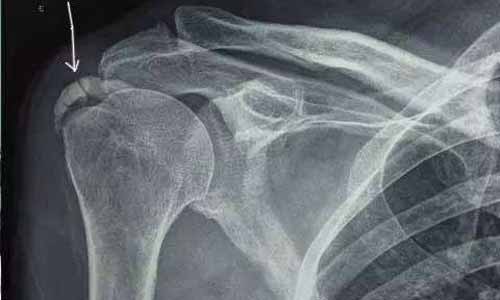

X线检查:右肩关节骨质疏松,骨密度较低,肩峰下滑囊钙化;膝关节软组织肿胀,关节面破坏,关节间隙狭窄。

(图:X线片显示马奶奶的右肩可见巨大钙化灶)